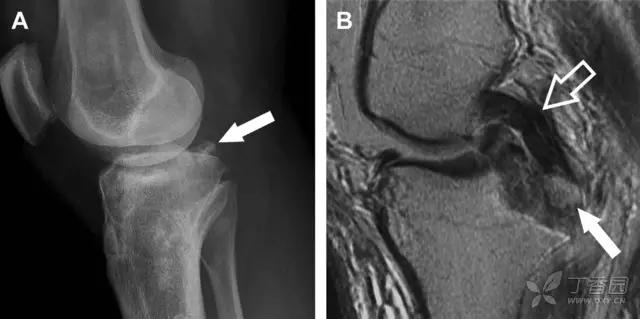

14 后交叉韧带胫骨髁间嵴

后方撕脱性骨折

约 6% 的后交叉韧带断裂与撕脱性骨折有关。X 线片特征表现为膝关节侧位片上可见大小不等的三角形骨折碎片移位到关节内(图 7)。

图 7 车祸后的后交叉韧带撕脱骨折

A 侧位片示后关节间隙见一移位的三角形骨折碎片(箭头)。B 矢状位 MRI 图像示骨折碎片(实箭头)附着于后交叉韧带上(空箭头)。